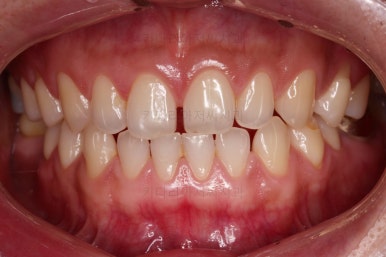

초진 시의 입안 모습입니다.

어금니가 빠져서 결손치아가 있고 치아 사이에 틈새도 있어서 교정치료도 함께 원한다고 내원해 주셨어요.

사진에서 보시는 바와 같이 윗니 1개, 아랫니 1개의 결손 부위가 보입니다.

윗니 어금니 중에는 신경치료를 마무리 못하고 임시재료로 메꿔뒀던 부위도 보이고요.